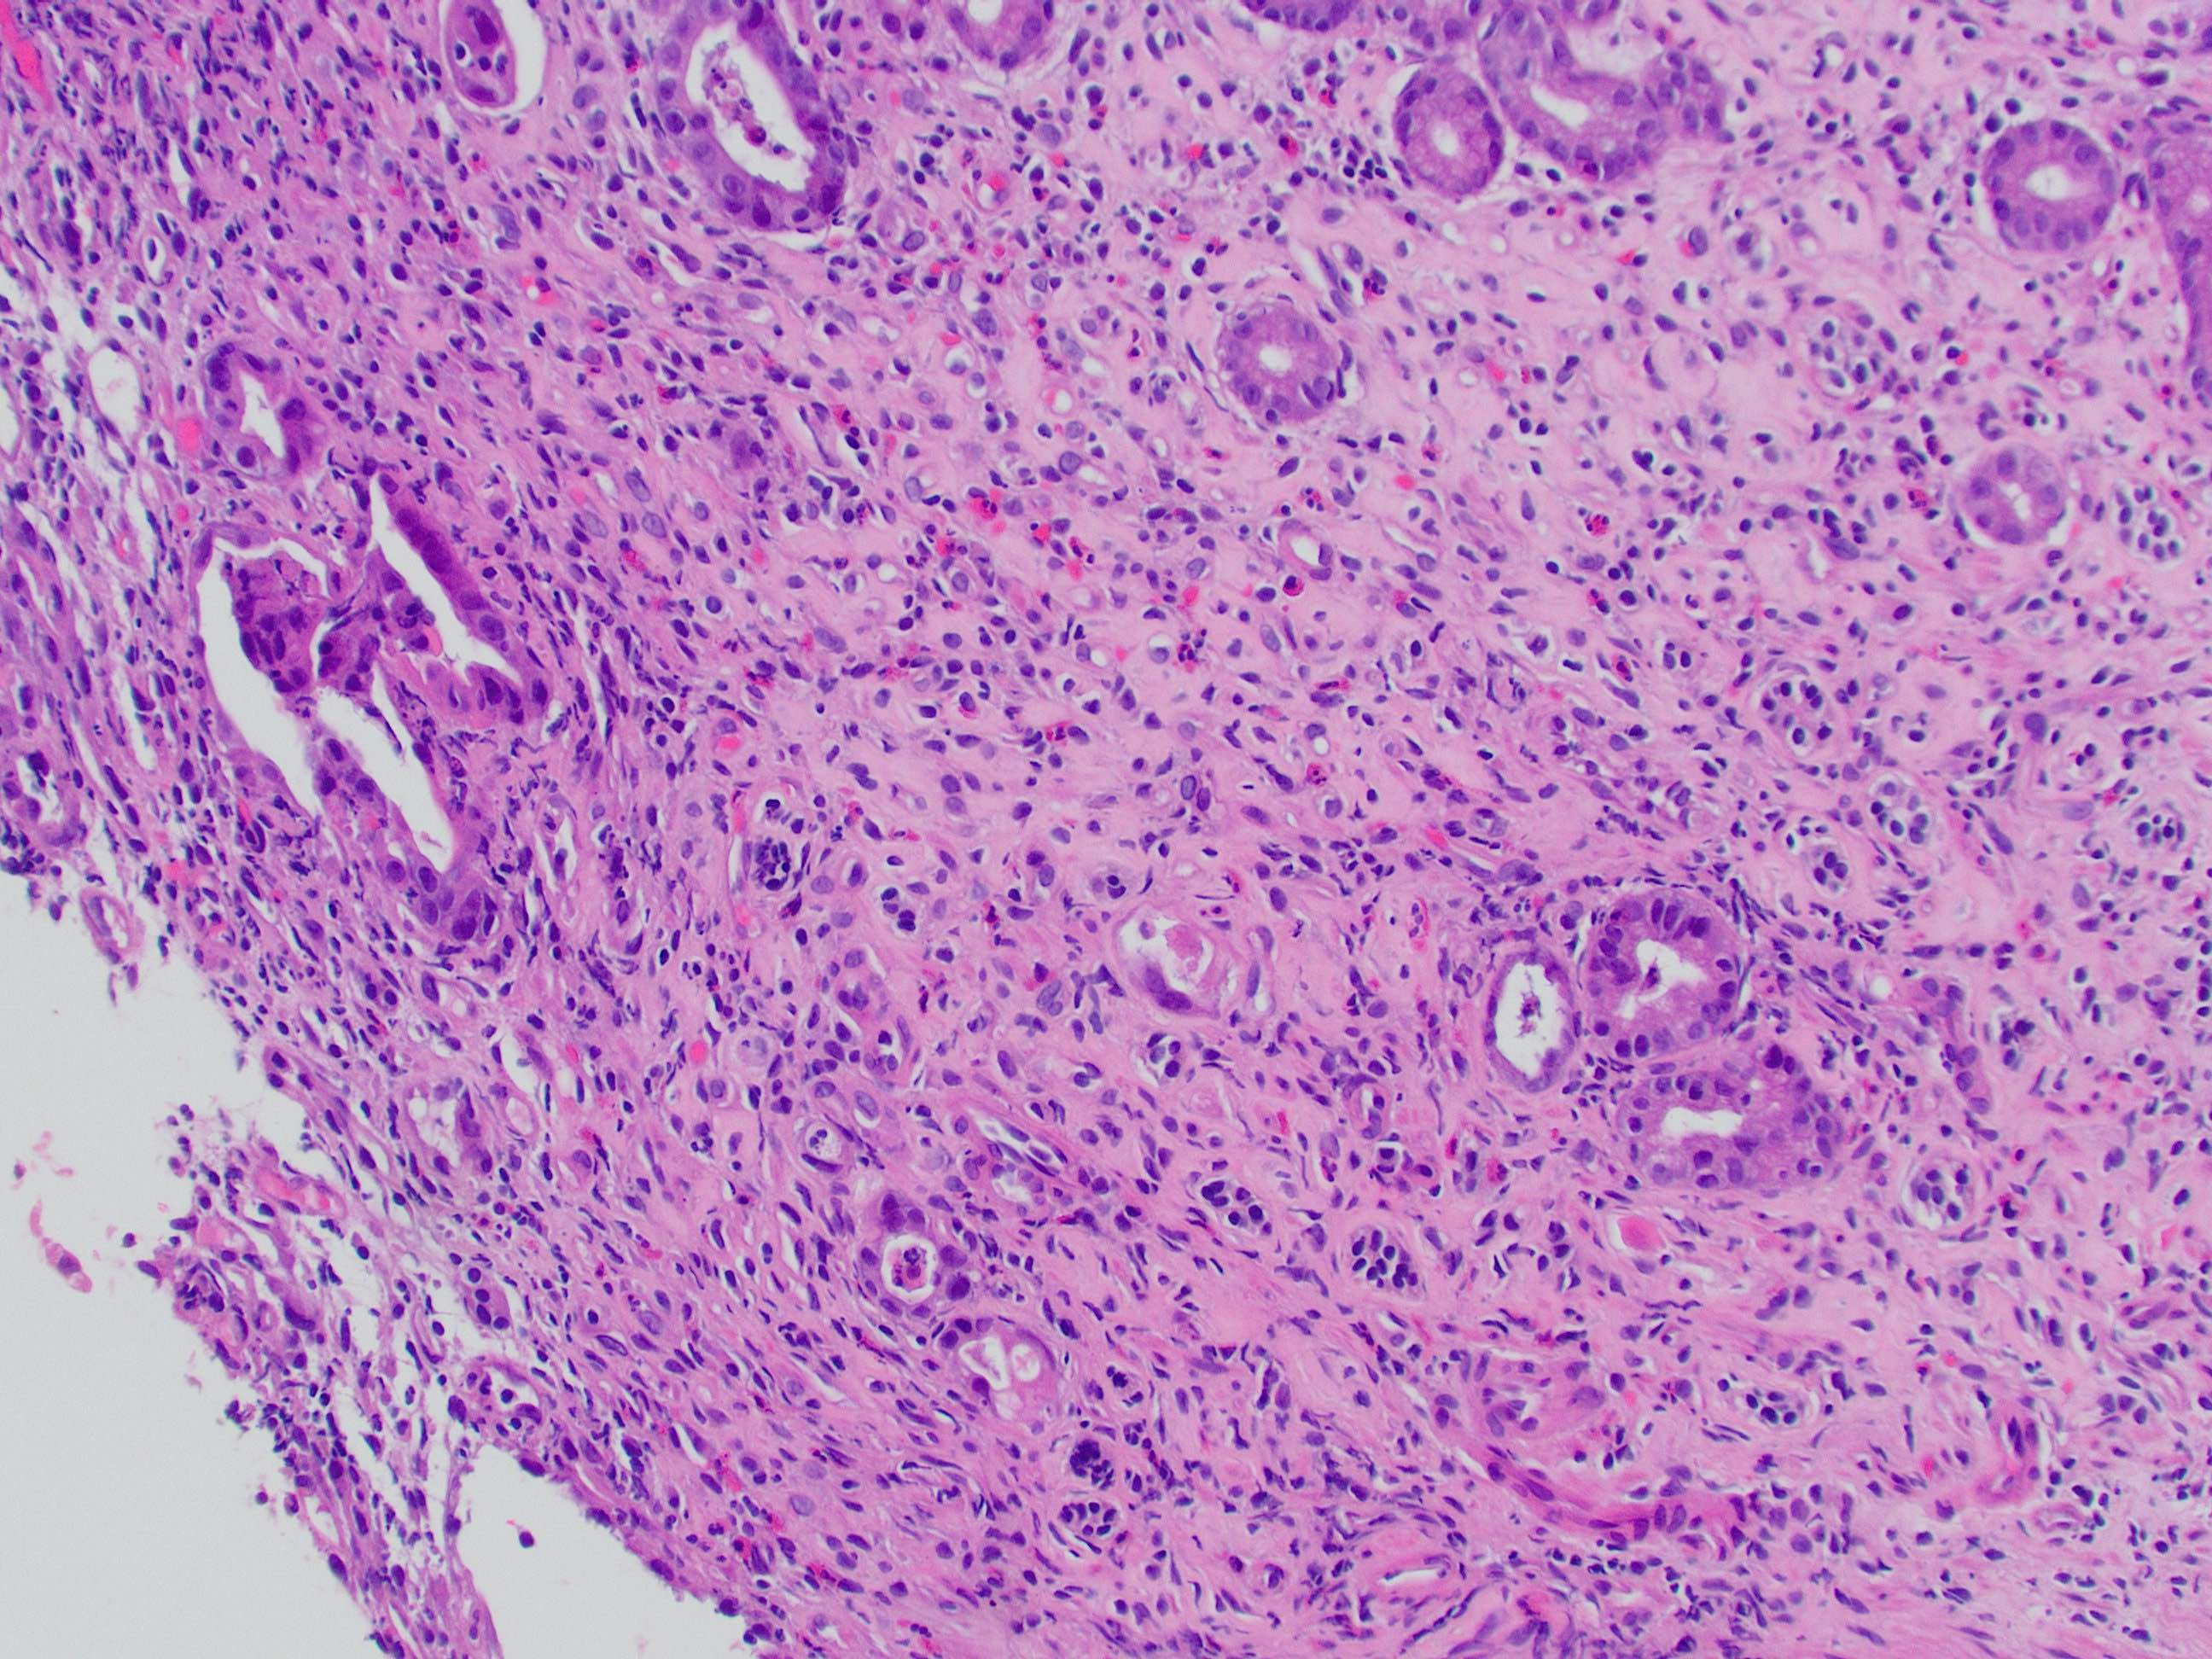

That covers the basics! Here is a direct side-by-side before and after editing in GIMP:

That covers the basics! Here is a direct side-by-side before and after editing in GIMP: